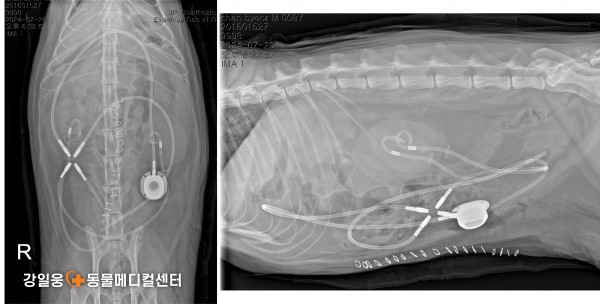

고양이 요관 폐쇄, SUB 수술로 새로운 길을 열다

SUB 수술(Subcutaneous Ureteral Bypass)

SUB 수술(Subcutaneous Ureteral Bypass) 은

요관이 막혔을 때 신장에서 방광으로 새로운 우회로

(인공 튜브)를 만들어 소변이 원활히 배출되도록 돕는 수술입니다.

쉽게 말해, 막힌 도로(요관)

대신 새로운 길을 만들어

신장에 고여 있던 소변이 다시 정상적으로

방광으로 내려가게 하는 수술입니다.

강일웅동물메디컬센터 정형·신경외과 전승하 원장은

그동안 다양한 원인으로 요관이 막힌 고양이들을 치료하며

여러 형태의 SUB 수술 사례들을 해결해 왔습니다.